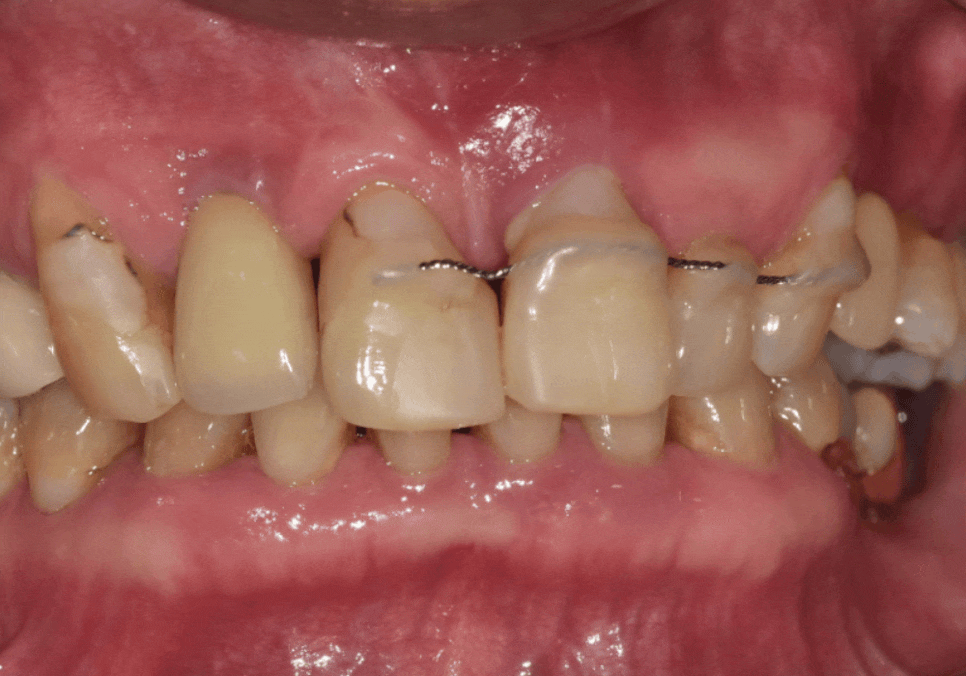

오른쪽 작은 어금니(#15)

:뼈이식을 동반한 임플란트 식립

흔들리는 앞니 (#11,21,22) : 발치 후

왼쪽 앞니 1개 (#22)

: 뼈이식을 동반한 임플란트 식립

여기서 부담을 줄일 수 있었던

핵심이 하나 더 있었어요.

환자분께는 오른쪽 앞니(#12) 부위에

기존 임플란트가 있었습니다.

250106 임플란트 보철 깨짐

도자기 계열로 씌운 임플란트 크라운이

깨져있는 모습이 보였습니다.

그래서 그 옆 치아 공간에 (#11)

새 임플란트를 하나 더 심기보다는,

250531 기존 임플란트 크라운 제거 후 힐링(단추)으로 바꾼 모습

오른쪽 앞니(#12)인 기존 임플란트와

왼쪽 앞니(#22 )에 임플란트 식립하여

브릿지로 연결하는 방향으로

설계를 조정했습니다.

250626

감액기간이지만 임플란트는

보장 50% 범위에서 진행을 도와드릴 수 있었고

뼈이식 내용도 보장되어,

필요 서류를 준비해 드린 덕분에

뼈이식 부분 또한 같이 보장받으셨습니다.

무엇보다 임플란트 1개를 추가로

식립하는 비용 부담을 줄이는 데

도움이 됐습니다.

250106 (전) 250626 (후)